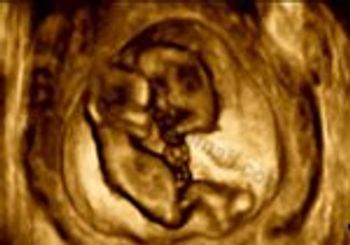

Several recent studies have shown that the addition of secondary ultrasound markers to the combined first-trimester screening for aneuploidies, or chromosomal abnormalities such as trisomy 21 (Down syndrome) and trisomy 18 (Edwards syndrome), can slightly improve screening accuracy.